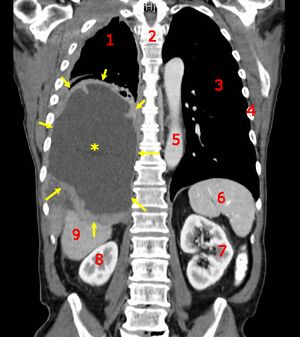

CT scan of a patient with mesothelioma, coronal section (the section follows the plane that divides the body in a front and a back half). The mesothelioma is indicated by yellow arrows, the central pleural effusion (fluid collection) is marked with a yellow star. Red numbers: (1) right lung, (2) spine, (3) left lung, (4) ribs, (5) descending part of the aorta, (6) spleen, (7) left kidney, (8) right kidney, (9) liver.